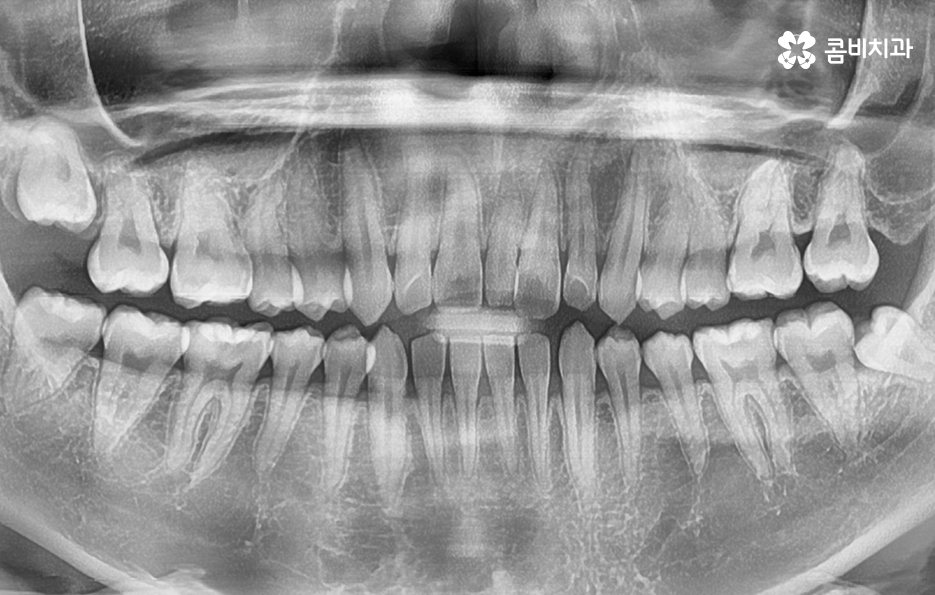

출처 아카이브 열기사람의 치아는 사랑니를 제외하면 위, 아래 모두 28개이고 사랑니는 보통 4개가 자라지만 요즘 아예 안나시는 분들도 있고 1~3개만 나시는 분들도 있어요. 과잉치는 정상적인 치아 개수 범위에서 초과하여 자라는 치아를 과잉치라고 하며 잇몸 속에 숨어 있어서 정상 치아의 맹출을 방해하는 요소가 되기도 하고 정상치아의 배열처럼 자라는 경우도 있는데 대체적으로 왜소하게 자라거나 기형적으로 자라는 형태를 보이고 있어요

과잉치가 있다고 하여 존재만으로 무조건 발치를 해야 하는 것은 아니며 환자분들의 상황에 따라서 적절한 1:1 맞춤형 치료로서 접근해야 하지만 오늘의 사례는 앞니의 중심부에 위치한 과잉치를 발치하고 앞니만교정을 한 사례를 소개해드릴 거예요

과잉치 중에서는 어떤 치아가 과잉치인지 구분이 어려울 정도로 일반적인 정상 치아의 크기와 비슷한 크기와 형태를 띄는 경우도 있는 반면에 위 사진의 케이스는 첫번째 앞니와 앞니 사이에 유독 작은 왜소치가 있는 형태이기 때문에 치아의 기능적인 문제 보다는 심미적인 개선을 필요했던 케이스로 볼 수 있어요

과잉치로 인해 말그대로 치아의 정상 범위 이상으로 치아가 배열되기 때문에 다른 치아의 배열에도 악영향을 주는 경우가 많지만 위 환자분의 케이스의 경우에는 치열 자체는 전체적으로 가지런한 편이라는 점과 특히 턱뼈가 넓은 편이라는 점에서 전체교정을 하지 않았어도 환자분이 원하는 치료의 목표는 달성할 수 있었어요